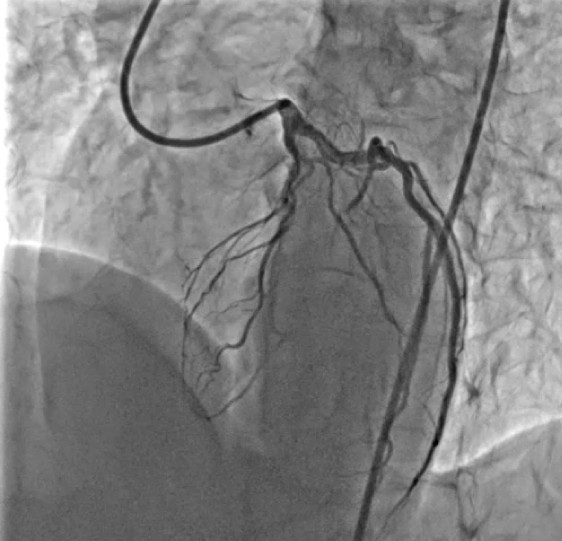

- A 7F EBU 3.5 guide catheter was used to selectively engage the left coronary artery, providing support for both antegrade and retrograde maneuvers.

- Well-developed septal-to-septal collateral channels connecting the proximal septal branch of the LAD or LCX to distal LAD septal branches were identified and deemed suitable for retrograde approach.A Sion wire was advanced into the donor septal branch through the same guide catheter. Over the wire, a Corsair Pro XS microcatheter was carefully navigated through the septal collateral to reach the distal true lumen of the LAD, under fluoroscopic roadmap guidance

- Using a Gaia Second wire, the CTO segment was crossed retrogradely from the distal LAD into the proximal true lumen of the LAD.

- The microcatheter was advanced to provide support and facilitate wire manipulation.

- An antegrade 1.5 mm balloon was positioned proximal to the occlusion.

- The balloon was inflated to create a controlled subintimal space (Reverse Controlled Antegrade and Retrograde Subintimal Tracking).

- The retrograde wire was maneuvered into the antegrade guide catheter through the subintimal space.Sequential balloon dilatation was performed to prepare the occluded segment.Overlapping drug-eluting stents (DES) were deployed to cover the entire length of the CTO.Final angiography demonstrated TIMI 3 flow in the LAD with no residual stenosis or complications.